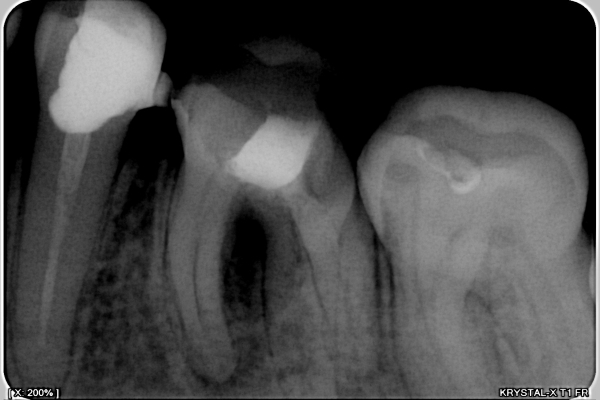

Беспокоят 2 зуба, точнее то, что один из них жевательная шестерка снизу сломалась, а на противоположной стороне отлетела пломба. По снимкам, один врач предложил удалить оба зуба, и поставить мосты. Другой врач предложил удалить только с одной стороны (36), а на другой (46) надеть коронку, но там у меня свищ.

Вам предстоит удаление и 3.6 и 4.6 зубов.

Нецелесообразно вкладывать деньги в зуб, в котором повсюду воспаление. Ни один врач, который вам действительно захочет помочь, не наденет на него коронку.